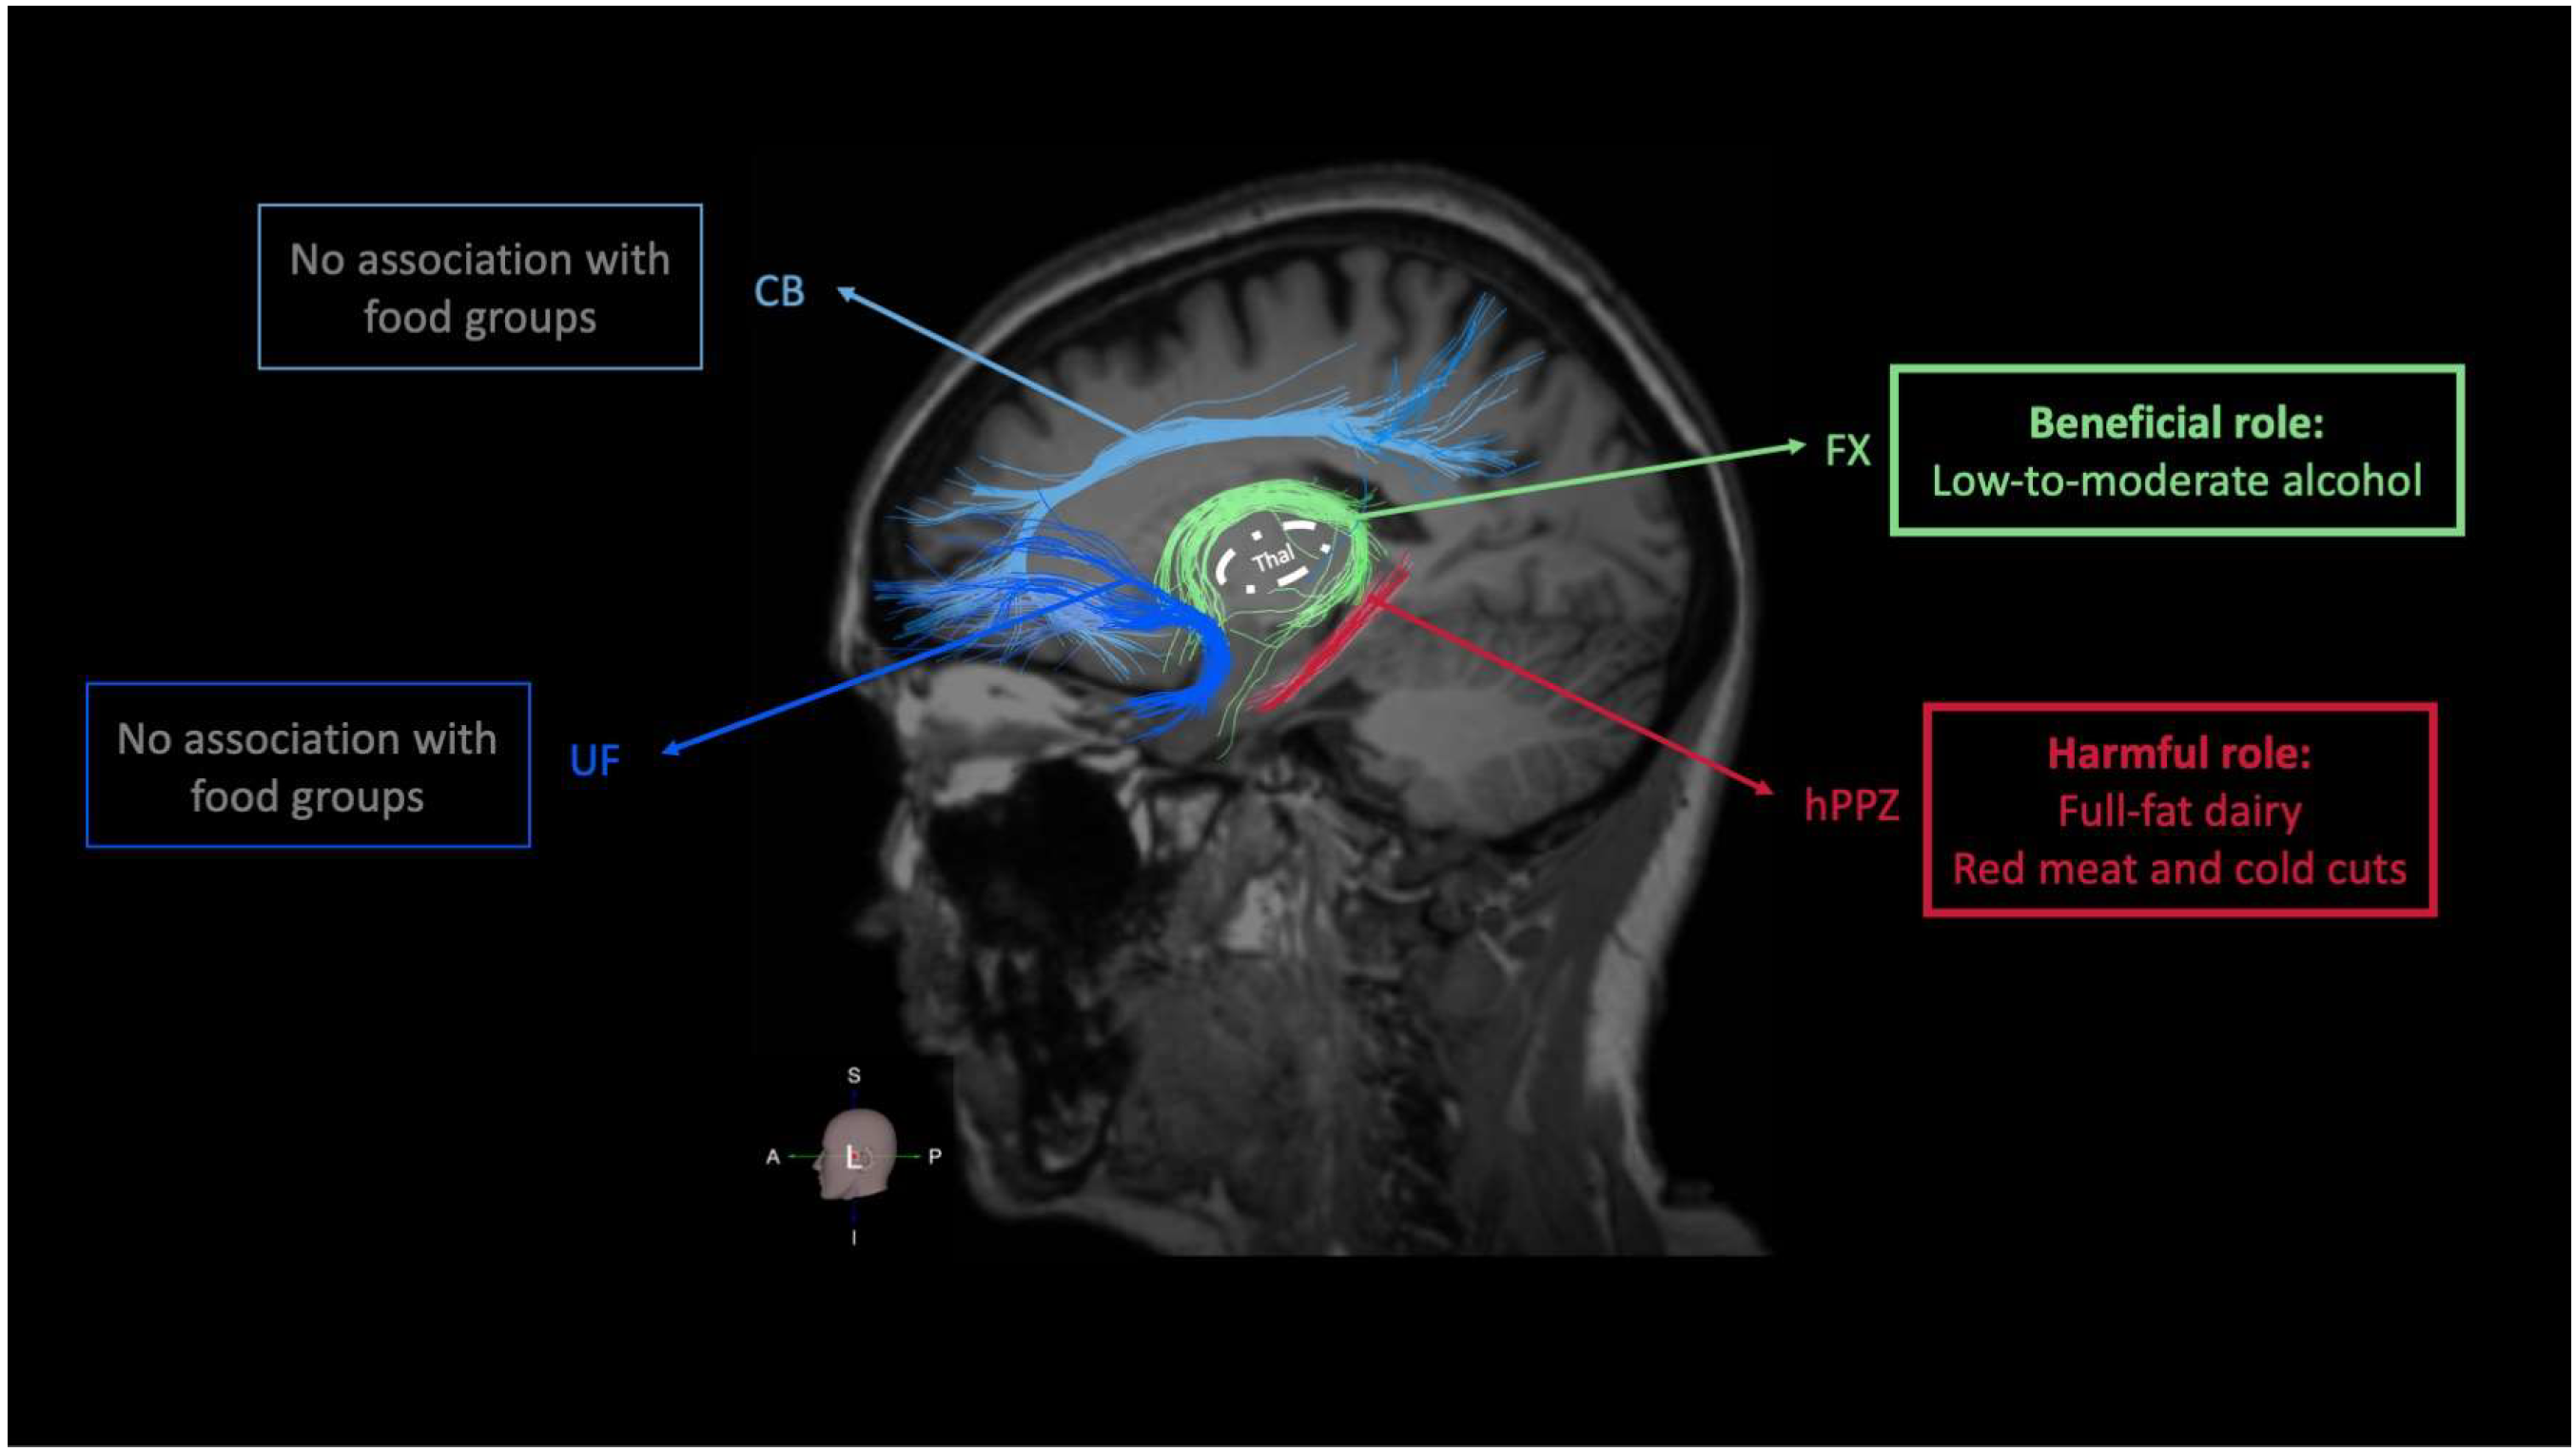

3.3. Food Groups and Integrity of Memory-Related (Limbic) WM Tracts

3.4. Food Groups and Performance on Memory-Related Neuropsychological Tests

| Independent Variable: Food Groups | Dependent Variable: FA Value of WM Tract | |||

|---|---|---|---|---|

| CB FA | UF FA | FX FA | hPPZ FA | |

| Non-refined cereals | B = 3.078E-5 [CI: −0.003 to 0.003], p = 0.985 | B = 0.002 [CI: 0.000 to 0.004], p = 0.114 | B = 0.001 [CI: −0.002 to 0.005], p = 0.551 | B = 0.002 [CI: −0.001 to 0.005], p = 0.164 |

| Fruits, vegetables, legumes | B = 0.000 [CI: −0.002 to 0.002], p = 0.864 | B = −0.001 [CI: −0.002 to 0.001], p = 0.351 | B = −0.001 [CI: −0.003 to 0.002], p = 0.597 | B = 0.000 [CI: −0.002 to 0.002], p = 0.797 |

| Fish | B = 0.004 [CI: −0.004 to 0.012], p = 0.359 | B = 0.002 [CI: −0.003 to 0.007], p = 0.421 | B = 0.000 [CI: −0.009 to 0.009], p = 0.965 | B = 0.004 [CI: −0.003 to 0.011], p = 0.315 |

| Full-fat dairy | B = −0.002 [CI: −0.009 to 0.004], p = 0.515 | B = −0.003 [CI: −0.007 to 0.001], p = 0.125 | B = −0.001 [CI: −0.008 to 0.006], p = 0.732 | B = −0.006 [CI: −0.011 to −0.001], p = 0.029 |

| Red meat and cold cuts | B = −0.003 [CI: −0.008 to 0.002], p = 0.276 | B = −0.002 [CI: −0.005 to 0.001], p = 0.229 | B = −0.002 [CI: −0.008 to 0.004], p = 0.473 | B = −0.007 [CI: −0.011 to −0.003], p = 0.002 |

| Alcohol | B = 0.000 [CI: −0.010 to 0.010], p = 0.968 | B = 0.003 [CI: −0.003 to 0.009], p = 0.337 | B = 0.014 [CI: 0.004 to 0.025], p = 0.009 | B = 0.006 [CI: −0.002 to 0.014], p = 0.141 |